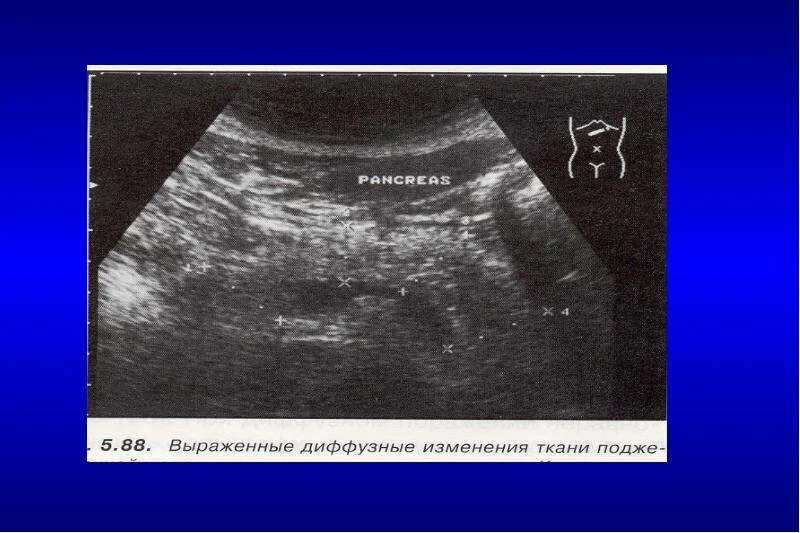

Выражена диффузные изменения поджелудочной железы